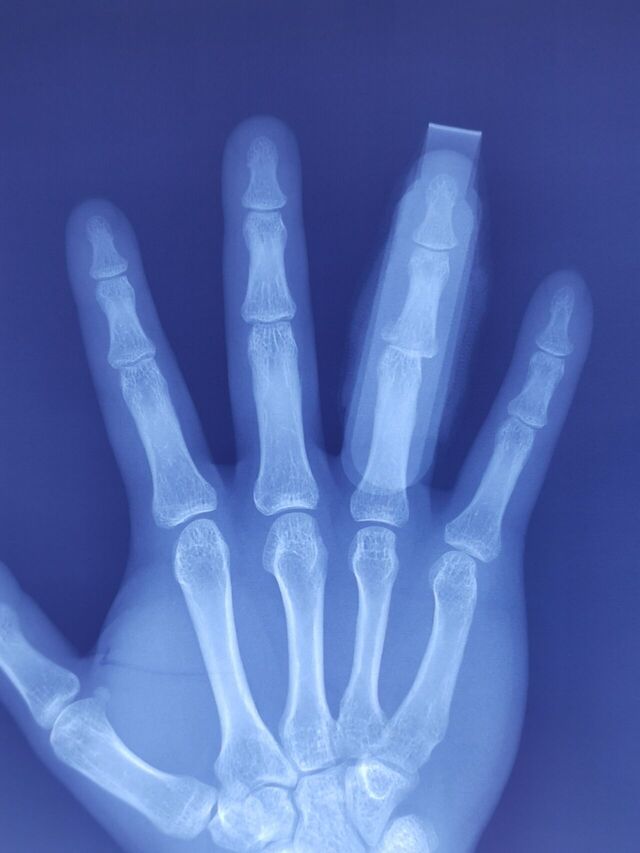

外伤后15天

怎么治疗?